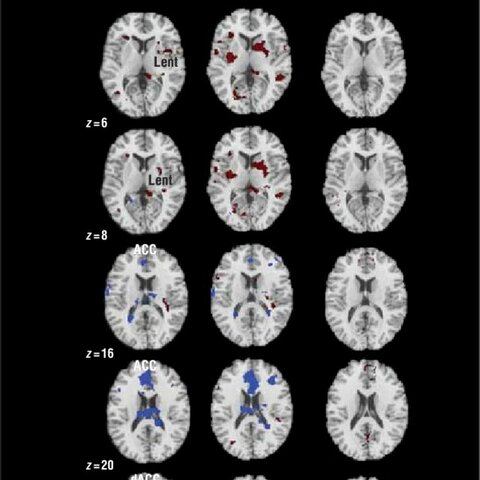

• science

Atlas mas completo sobre la arquitectura del cerebro